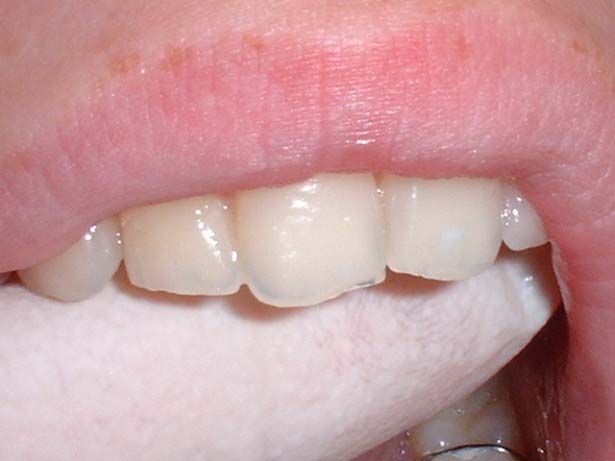

Another useful aid is to move a gloved finger behind the upper incisor teeth tips looking for translucency.

Gloved finger test